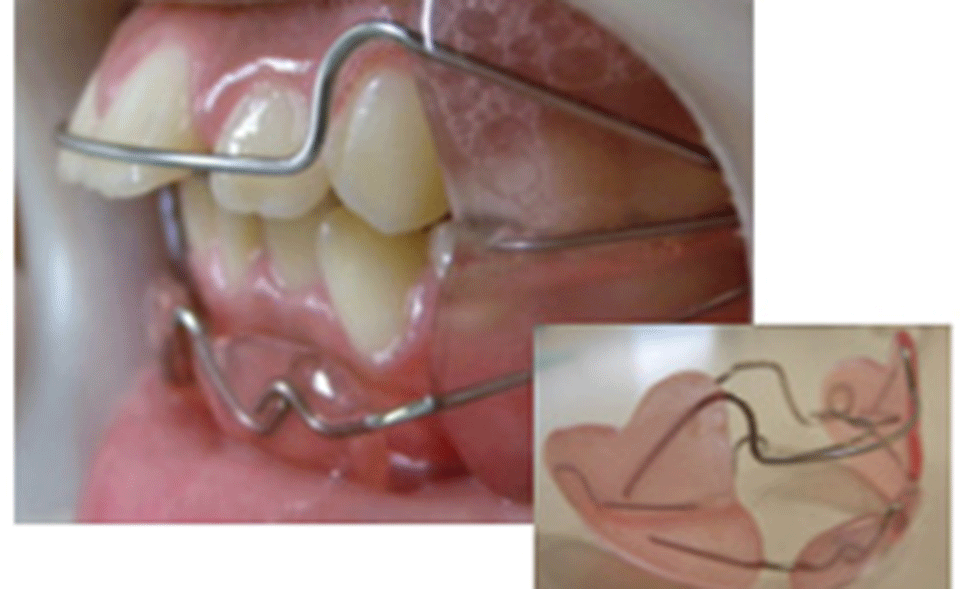

(3)院長はTip-Edge矯正研究学会の指導医です

院長の小島は、Tip-Edge矯正研究学会の専門医で、研修会においてはインストラクターとして多くの若い歯科医師の先生を指導しています。

また、アメリカ・ハーバード大学教授 矯正専門医 宮島邦彰教授も治療を行います。

矯正治療についてより詳しく学べる環境があります。